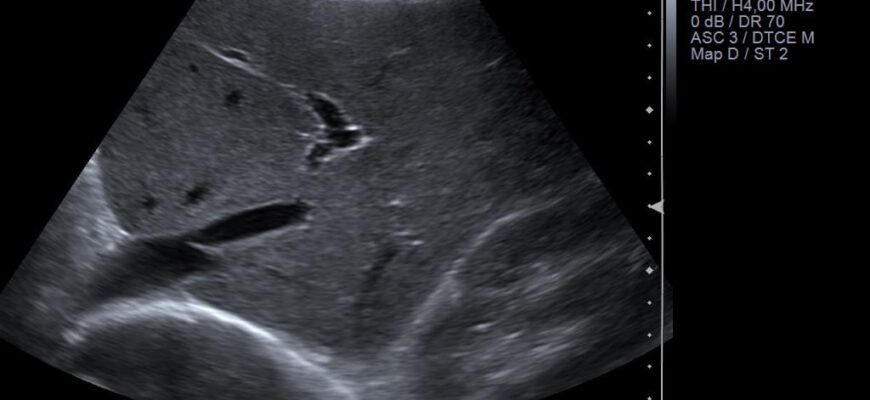

Завдяки цьому режиму ми можемо отримати надзвичайно чіткі та контрастні зображення. Ультразвукові хвилі, що відбиваються від внутрішніх структуру тіла, на екрані перетворюються у монохромну гаму. Чорно-біле зображення дозволяє лікарям розгледіти навіть найменші деталі, які можуть бути пропущені при інших методах діагностики.

Суть роботи УЗД полягає в застосуванні звукових хвиль високої частоти, які проникають в організм і відбиваються від різних органів та тканин. Ці відбиті хвилі сприймаються датчиком і перетворюються на візуальні зображення на екрані. У режимі сірої шкали кожна структура проявляється у відтінках сірого, що дає змогу виявити навіть найменші зміни в органах.